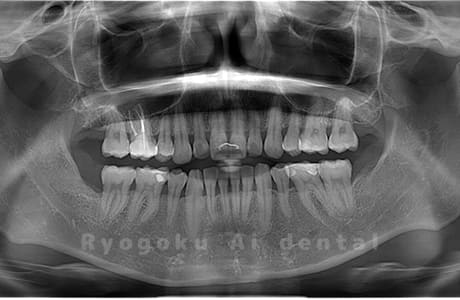

真っ直ぐ生えている親知らず

親知らずが真っ直ぐ生えているタイプです。

このタイプは真っ直ぐ生えていて咬み合わせに問題がなければ、抜歯しないケースもあります。ただし、虫歯になっていたり、痛みがあったり、咬み合わせが悪かったりすると抜歯をおすすめします。